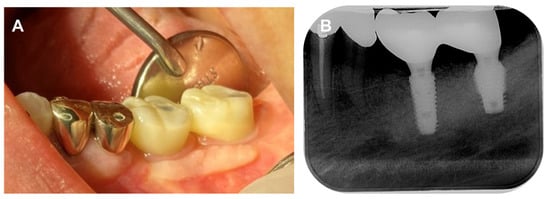

The final prosthesis was connected to the multi-abutments through the abutment screw in the oral cavity of the patient. After the intraoral adjustment, the prosthesis was connected to the implants through the abutment screw with a torque of 25 N/cm2. Teflon tape and composite resin were used to seal the screw access holes (Figure 11A) and the accurate connection of the implant prosthesis was evaluated through using a periapical radiograph (Figure 11B).

Figure 11. Final delivery of implant prosthesis. (A) Intraoral photograph, (B) Periapical radiograph.